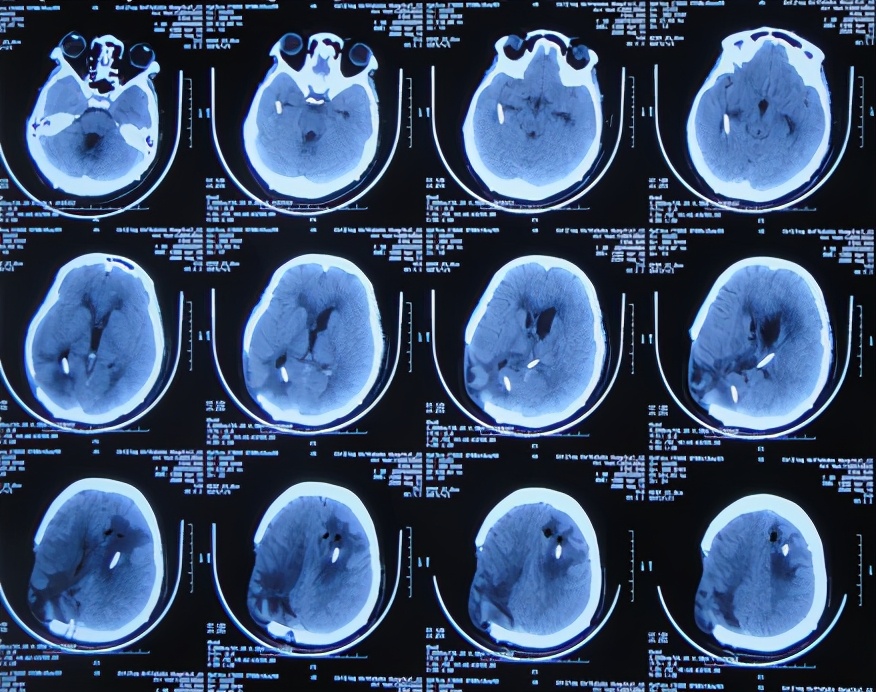

开颅术后次日即2020年4月3日,意识恢复,可简单言语,但左侧肢体偏瘫,仅可在床面平移,伴发热体温最高39.0℃;复查头颅CT示开颅术后去骨瓣状态,出血有减少,引流术后状态( 图-2 )。

图-2: 2020年4月3日头颅CT

开颅术后第2天即2020年4月4日,仍发热,给予腰椎穿刺释放血性脑脊液。

开颅术后第3天即2020年4月5日,因出血明显减少,拔除了脑室外引流管( 图-3 )。

图-3: 2020年4月5日头颅CT